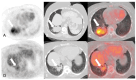

Systemic vasculitides are a rare and complex group of diseases that can affect multiple organ systems. Clinically, presentation may be vague and non-specific and as such, diagnosis and subsequent management are challenging. These entities are typically classified by the size of vessel involved, including large-vessel vasculitis (giant cell arteritis, Takayasu's arteritis, and clinically isolated aortitis), medium-vessel vasculitis (including polyarteritis nodosa and Kawasaki disease), and small-vessel vasculitis (granulomatosis with polyangiitis and eosinophilic granulomatosis with polyangiitis). There are also other systemic vasculitides that do not fit in to these categories, such as Behcet's disease, Cogan syndrome, and IgG4-related disease. Advances in medical imaging modalities have revolutionized the approach to diagnosis of these diseases. Specifically, color Doppler ultrasound, computed tomography and angiography, magnetic resonance imaging, positron emission tomography, or invasive catheterization as indicated have become fundamental in the work up of any patient with suspected systemic or localized vasculitis. This review presents the key diagnostic imaging modalities and their clinical utility in the evaluation of systemic vasculitis.